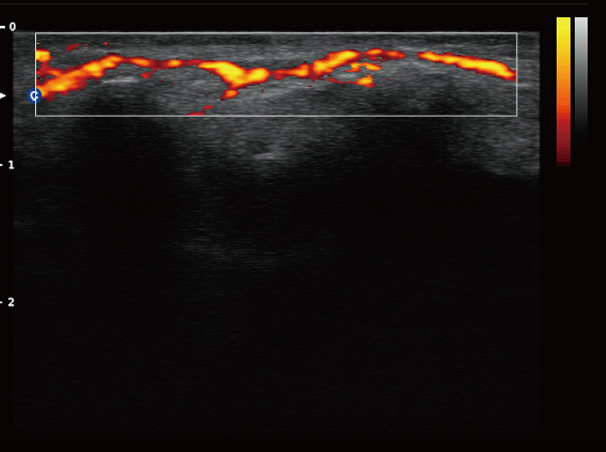

Chison Qbit 3 Color Doppler Digital Ultrasound Machine

Chison Qbit 3 A Slim Console Color Doppler System, Offers Ideal Patient Care With Its Easy Mobility, Smart Features, Significant Performance And Streamlined Workflow, To Strengthen The Clinical Confidence And Speed The Diagnostic Decision.

QBit 3 Slim.Smart.Significant.Streamlined

Chison Qbit 3 Ultrasound Machine

Chison QBit-3 Ultrasound Machine System, Offers Ideal Patient Care With Its Easy Mobility, Smart Features, Significant Performance And Streamlined Workflow, To Strengthen The Clinical Confidence And Speed The Diagnostic Decision.